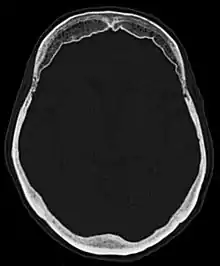

فرط تعظم باطن العظم الجبهي كما يظهر بواسطة الأشعة المقطعية.

فرط تعظم باطن العظم الجبهي (باللاتينية: Hyperostosis frontalis interna) هو تسمك حميد شائع يحدث في الجزء الداخلي من العظم الجبهي من الجمجمة. يحدث غالبا في النساء في سن اليأس وغالبا من يكون بدون أعراض. غالبا ما يكتشف بشكل عرضي خلال الفحوص بالأشعة السينية والأشعة المقطعية للجمجمة.[1]